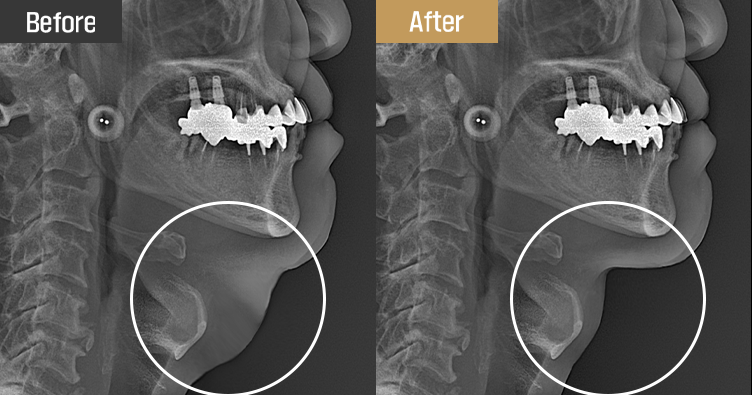

Personalized design through precise diagnosis

Drawing on our extensive anatomical knowledge, we develop a customized plan for each patient

using X-rays and facial ultrasound. By carefully evaluating fat thickness, skin sagging, muscle laxity,

and salivary gland enlargement, we ensure safe and reliable results.

Patients can immediately verify the effects with an X-ray right after surgery.

Visible results you can see for yourself

The results can be seen instantly with an X-ray following surgery.